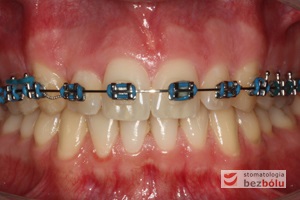

Młody 28-letni, pogodny, stale uśmiechnięty pacjent zgłosił się celem korekcji wad zębowych ograniczających pełną ekspresję uśmiechu. Głównym problemem był dodatkowy siekacz boczny (dwójka) po stronie prawej w łuku górnym. Dodatkowy ząb spowodował stłoczenia pozostałych zębów w łuku górnym oraz przesunięcie linii pośrodkowej. Obliczenia dostępnego miejsca dla siekacza bocznego wpłynęły na wybór zęba przeznaczonego do ekstrakcji. Usunięto dwójkę ustawioną dowargowo, zaś jej „siostrę bliźniaczkę” skierowaną w stronę podniebienia wprowadzono do łuku zębowego w drodze leczenia ortodontycznego. Problemem było szczelne zamknięcie szpary poekstrakcyjnej z powodu nadmiaru miejsca w kości. Wyrównano linię pośrodkową. Leczenie przeprowadzono jednym łukiem ortodontycznym górnym, dolny łuk zębowy nie wymagał założenia aparatu. Po zdjęciu zamków korekcję detali przeprowadzono z użyciem pozycjonera wykonanego w technice termoformingu. Stabilizację efektów leczenia zapewnił stały retainer klejony do powierzchni podniebiennych siekaczy górnych.

Leczenie ortodontyczne: planowanie i aktywna faza leczenia, leczenie retencyjne – lekarz stomatolog Magdalena Żywicka i lekarz stomatolog Marta Pakuła